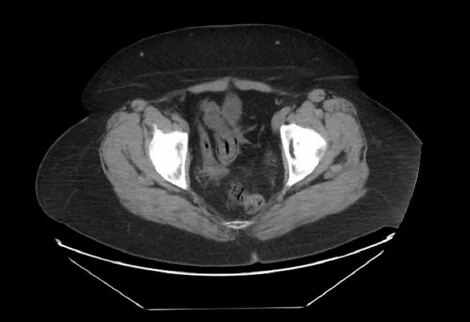

哎呀,说到这个肠套叠CT图,真是让人心惊胆战的!你知道吗,那种图一出来,医生们一个个都皱起了眉头,像是看到了什么不得了的大问题。我记得有一次,一个小朋友的家长拿着那张CT图来找我,脸上的表情比哭还难看。他们说,孩子肚子疼得厉害,做出来的CT图上,肠子就像是一条扭成了麻花的小蛇,真是让人看了心疼。

那图上的肠子,一层套一层,就像是玩偶里的小人儿,一个套一个,看得人眼花缭乱。医生说,这种情况要是不及时处理,孩子可是会有生命危险的。听到这话,家长的腿都软了,眼泪止不住地往下掉。我看着他们,心里也是五味杂陈,只能安慰说,医生们会尽全力救治的。